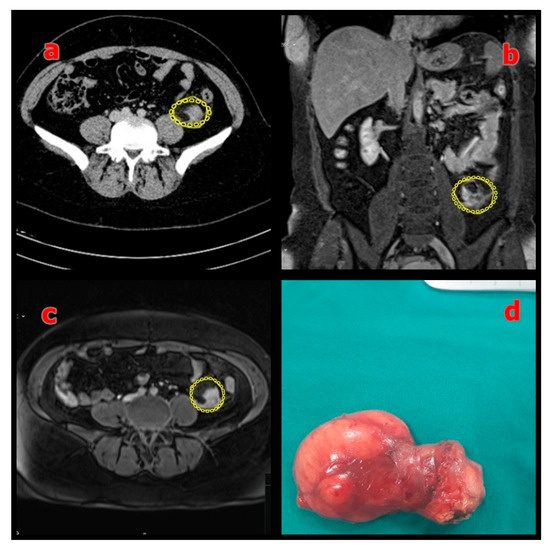

3.1. Patient and Tumor Characteristics